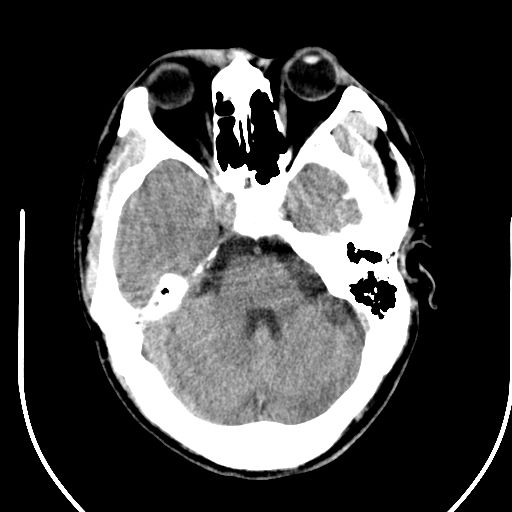

标题: CT25423:头部外伤意外发现右顶叶??? [打印本页]

标题: CT25423:头部外伤意外发现右顶叶???

ct值约13hu。

边缘清晰,没有占位效应,不像脑沟,结合ct值,软化灶可能吧

与脑沟没关系,小软化灶或陈旧性感染吧!

看样年纪不小了直接报腔梗,当然你要想报软化灶也是一样的

考虑右侧额叶巨腔隙灶;建议必要时行mri检查。